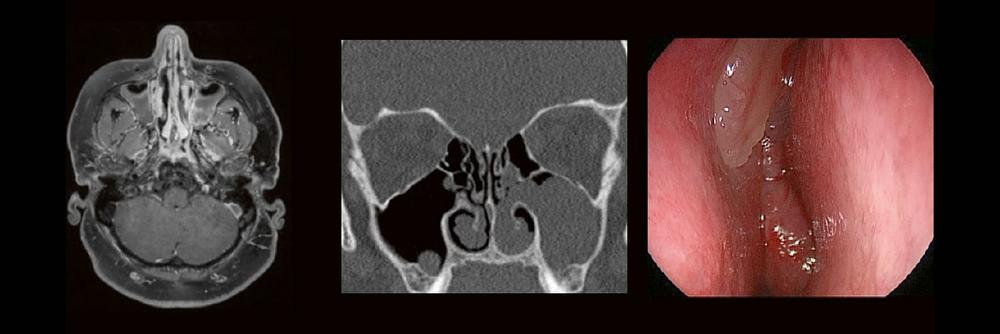

Die bildgebende HNO-Diagnostik macht es Anfängern nicht leicht. Die Anatomie ist komplex und weniger intuitiv als in anderen Körperregionen.

Normvarianten erschweren insbesondere in den Nasennebenhöhlen den Lernprozess. Sobald pathophysiologische Zusammenhänge verstanden und wichtige klinische Aspekte verinnerlicht wurden, gelingt es einen praxistauglichen, belastbaren Befund zu erstellen.

Gemeinsam mit einem HNO-Chirurgen werfen wir einen Blick IN die NNH – mal in grau, mal in Farbe. Denn alles fällt leichter, sobald man verstanden hat, warum man es tut.